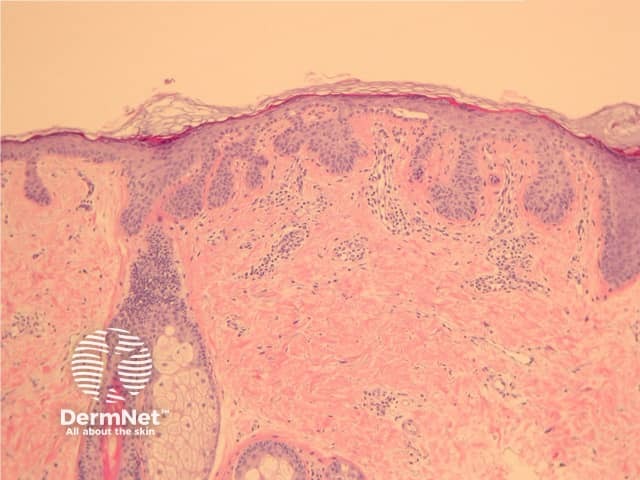

Epidermal changes in Dowling-Degos disease include hyperkeratosis, often with small horn cysts and thinning of the suprapapillary epidermis. Thin epithelial strands extend into the superficial dermis from the epidermis and hair follicles resulting in an ‘antler-like’ pattern (Figures 1, 2). Epidermal hyperpigmentation is usual although rare non-pigmented variants are reported. The hair follicle infundibulum may be dilated. Dermal perivascular lymphohistiocytic infiltrate (figures 1,2,3) or a lichenoid tissue reaction pattern may be seen.

Figure 1